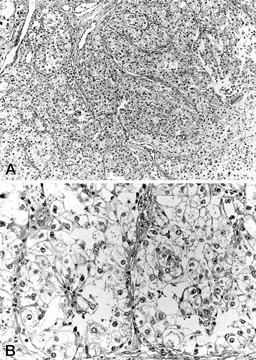

The histopathologic features of all tumors were similar, and closely mimicked those of clear cell carcinoma of the kidney. The neoplastic cells were arranged in sheets and packets traversed by a delicate vasculature consisting of a rich network of sinusoid-type blood vessels without extravasated red blood cells. Focally, there was a papillary-like pattern or pseudoglandular appearance (Fig. 1, A–B). The tumors comprised a rather uniform population of large polygonal cells with abundant cytoplasm. The tumor cells had a round to oval nucleus, sometimes with a prominent nucleolus, and exhibited mild to moderate nuclear pleomorphism. The cytoplasm was either entirely clear or partially clear but with interspersed fluffy eosinophilic areas. Case 4 was slightly different for a more pronounced eosinophilia of the cytoplasm and presence of only scanty glycogen (Fig. 2, A–B).

A, The large neoplastic cells are arranged in sheets and packets traversed by a delicate vasculature consisting of a rich network of sinusoid-type blood spaces. B, The pseudoglandular appearance combined with the clear cytoplasm of the neoplastic cells results in a strong mimicry of clear cell carcinoma of the kidney.